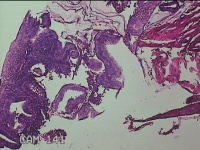

子宫腔组织

性别

女

年龄

47岁

临床诊断

异常子宫出血

一般病史

月经周期经期延长,月经量增多7天,超声提示子宫内膜11mm,回声不均。

标本名称

大体所见

灰白暗红色不规则碎组织1.5x1.3x0.3cm一堆。

子宫内膜增生症。